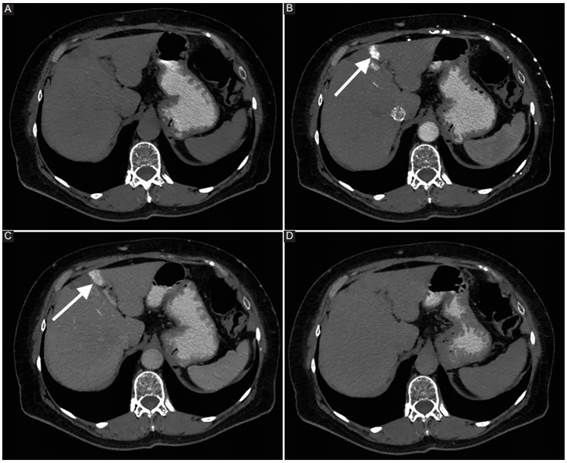

El área hipercaptante o hiperdensa se puede observar tanto en medicina nuclear como en tomografía computada (TC) con contraste endovenoso, y corresponde a un segmento hepático de mayor circulación debido a un mayor flujo sanguíneo a dicho nivel. La imagen en TC se describe como una zona de hiperdensidad en la fase arterial con forma de cuña, que lava parcialmente y se muestra levemente hiperdensa o isodensa en fase venosa (Fig. 2). Esto se explica por la generación de venas colaterales secundarias a la obstrucción del flujo venoso en la VCS con un shunt porto-sistémico. El sentido de dicho shunt generalmente se origina en la VCS, pasando por el sistema mamario interno hacia la vena umbilical recanalizada, y desde allí al sistema portal, generando el signo en cuestión2. De esta manera, se entiende que la hiperdensidad observada en la fase con contraste endovenoso se encuentra anatómicamente en el segmento correspondiente a la vena umbilical izquierda y las ramas izquierdas de la vena porta.